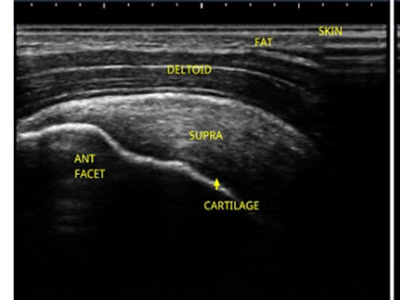

Why use ultrasound guidance for injections?

Prof. Nat Padhiar - MSK clinicians stethoscope and guidance system

Catch up here on last weeks webinar: Prof. Nat Padhiar - MSK clinicians stethoscope and guidance system

MSK Group Mentoring Course for Healthcare Professionals | Module 1 Shoulder (4 hours CPD)

We are delighted to announce details of our upcoming MSK Group Mentoring Course for Healthcare Professionals, Module 1 Shoulder. The online course will be accessible from Monday 31st May 2021 and is a flexible learning opportunity for health care professionals.